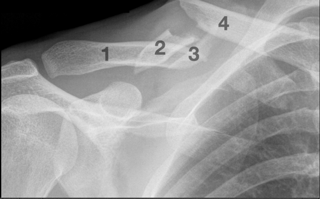

Fabian Cancellara has vowed to focus on a second Olympic title following the accident at Sunday’s Tour of Flanders that left him with a quadruple fracture in his collar bone and a wrecked spring Classics campaign.

The spring Classics would seem to be over for Cancellara, barring a super human recovery in time for Ardennes Week (remember, this is Spartacus), but the nature of his injury means that his entire season is far from wrecked. With an opportunity to claim a second gold medal at in the road time trial at this summer’s Olympics (he has already familiarized himself with the London parcours) all is far from lost for the Swiss champion.